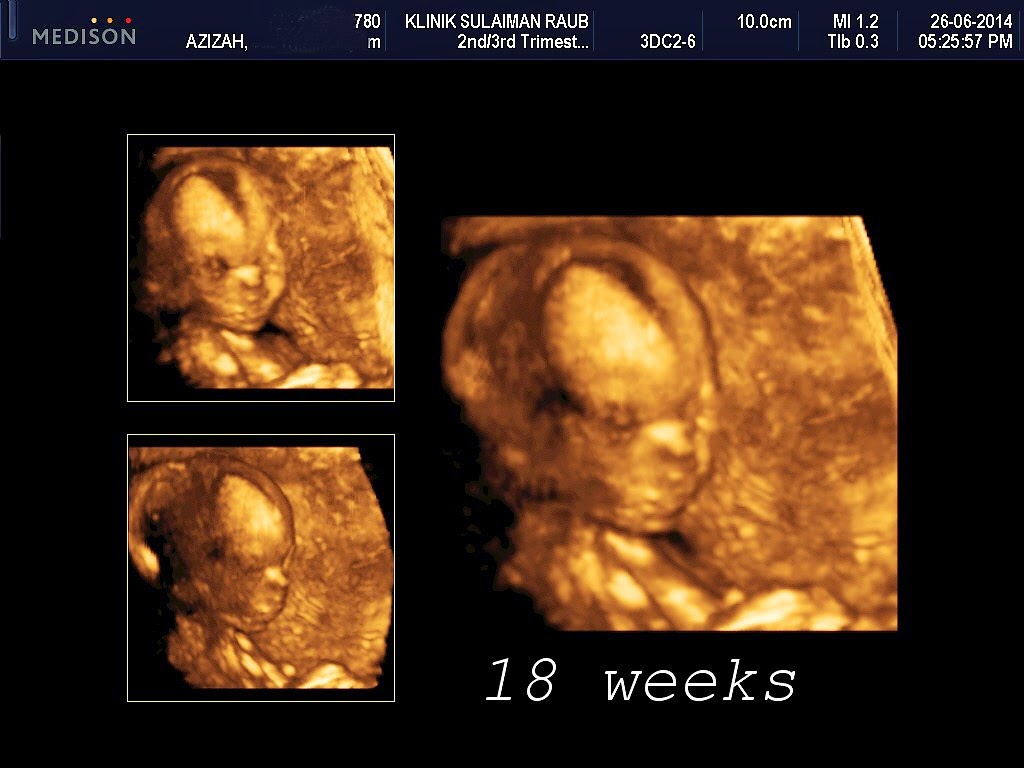

Sebelum 21 minggu. keseluruhan badan fetus boleh dilihat, tapi keadaannya nampak kurus / tulang / mungkin menakutkan.